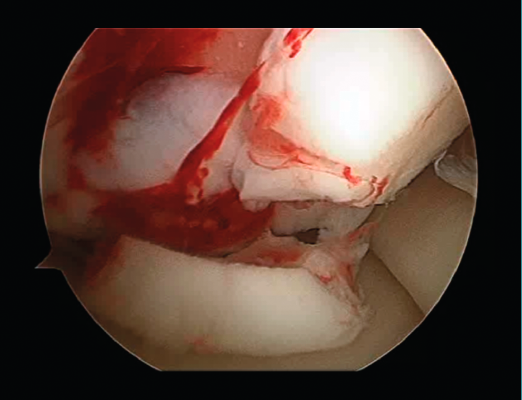

First surgery involves arthroscopy of the damaged joint. It assesses the chondral lesion to be treated and confirms whether it is amenable to the chondrocyte implantation technique (Figures 1 and 2). Other procedures are also carried out if needed, such as for example reconstruction of the anterior cruciate ligament, partial meniscectomies, meniscus implantation, patellar realignments, osteotomies, etc. Lastly, the cartilage sample is taken from a non-weight bearing zone (intercondylar zone or internal femoral condyle at its upper margin). The sample is extracted with biopsy forceps or, alternatively, using discectomy forceps. Between 3-4 rice grain-sized fragments of healthy cartilage are harvested (Figure 3). The biopsy material is placed in a sterile receptacle containing a culture medium (DMEN) (Figure 4). The material is kept at room temperature and is shipped to the laboratory as quickly as possible. A form should be completed (Figure 5), stating the joint, the location of the lesion and the size of the defect. Once in the laboratory, the sample is processed and cultured. After 4-6 weeks (depending on the case), the culture is ready for implantation.